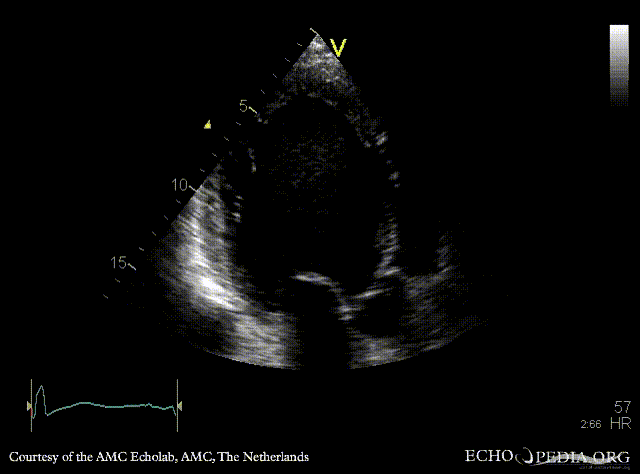

| Courtesy of: AMC Echolab, AMC, The Netherlands | |

| PLAX: Dilated left ventricle with poor function | A4CH |